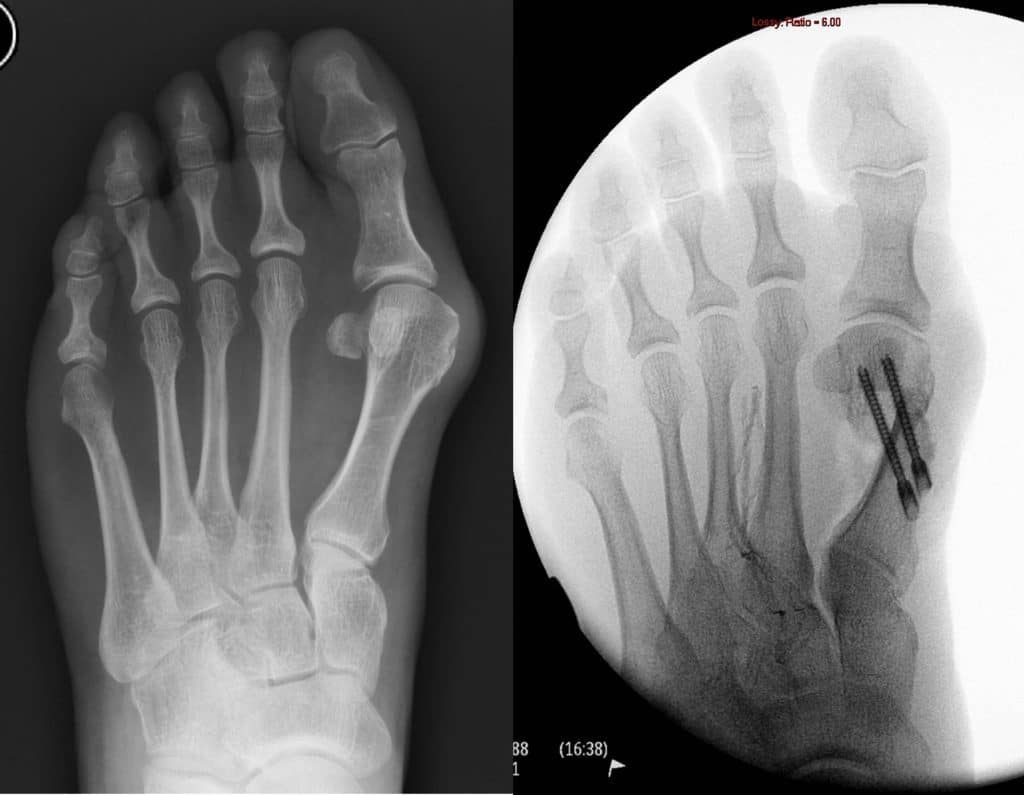

• Fracture fixation with plates/screws.

• Osteotomy/fusion for bunions or arthritis.